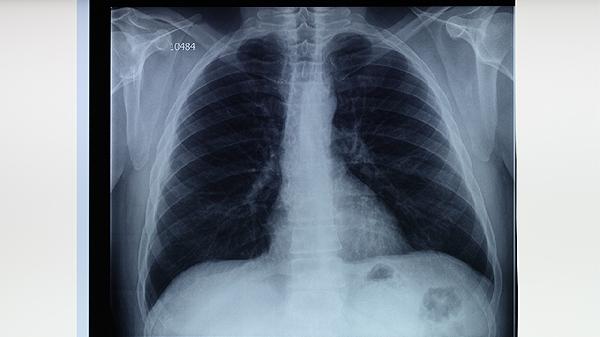

預防肺結(jié)核疾病可通過接種卡介苗、保持良好通風、避免密切接觸患者、增強免疫力、定期篩查等措施實現(xiàn)。肺結(jié)核是由結(jié)核分枝桿菌引起的慢性傳染病,主要通過呼吸道傳播。

結(jié)核菌素試驗和γ-干擾素釋放試驗可用于潛伏感染檢測。高危人群如醫(yī)務(wù)人員、矽肺患者應(yīng)每年進行胸部X線檢查。出現(xiàn)持續(xù)咳嗽、低熱、盜汗等癥狀超過2周時,需及時做痰涂片和痰培養(yǎng)檢查。